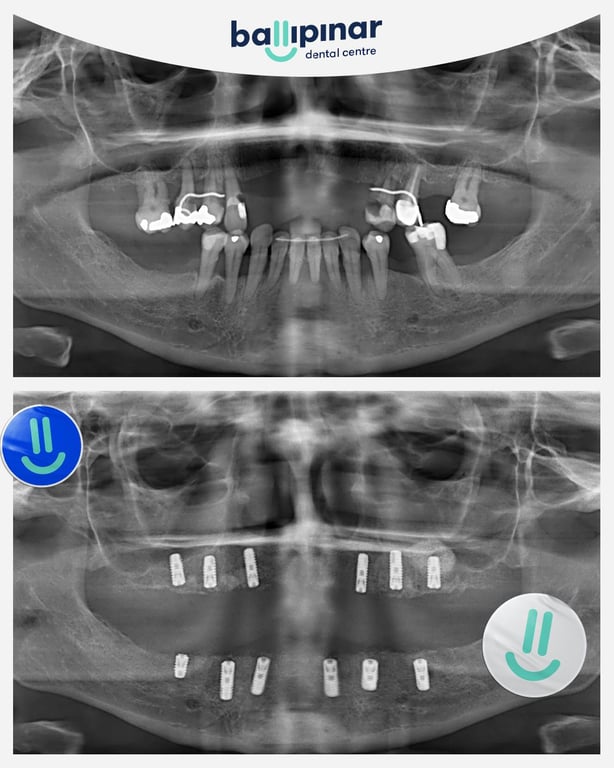

Dental implants Before & After

Explore all the before and after photos of dental implant procedures performed by Ballipinar in Turkey. Contact us today to achieve a beautiful smile.